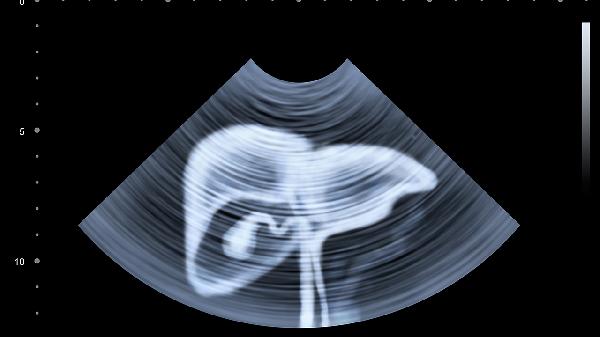

进食后胃内食物残渣和气体可能遮挡部分器官结构,增加误诊概率。食物消化过程中产生的肠蠕动伪影会影响图像清晰度,尤其对胰腺、胆管等细小结构的显示可能产生干扰。高脂肪食物可能刺激胆囊收缩,导致胆囊壁增厚假象。含碘食物可能影响血管成像质量,干扰出血或血栓的识别。胃内液体可能被误判为腹腔积液或囊肿性病变。

急诊情况下医生可能根据病情需要立即进行CT检查,此时少量进食的干扰可通过调整扫描参数部分弥补。部分医院对儿童或糖尿病患者会放宽空腹要求,允许检查前2小时进食少量流质食物。增强CT检查前通常允许饮用少量清水保持血管充盈度,但需严格避免含糖饮料。某些特殊检查如肠道CT造影需要提前服用对比剂,此时饮食限制会有相应调整。